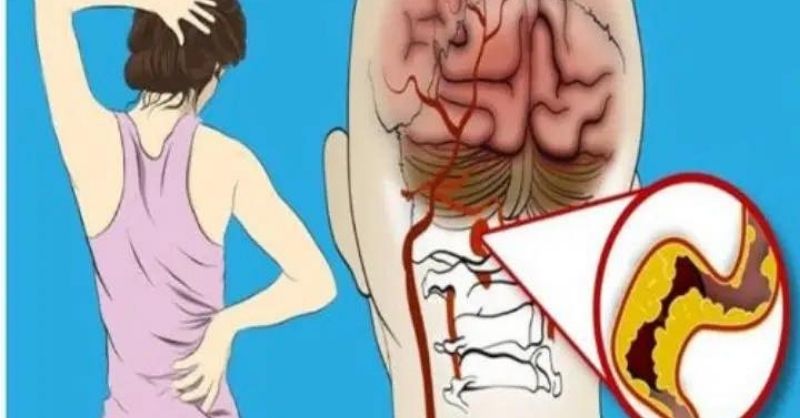

10 Unusual Signs of Str0ke in Women

A stroke can happen to anyone, but women are more likely to experience symptoms that differ from those commonly seen in men. In some cases, these symptoms can...